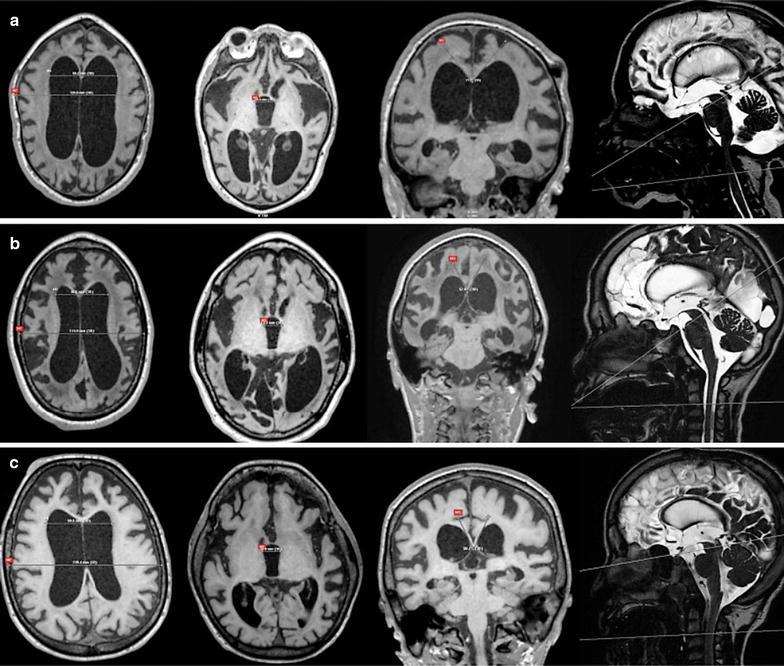

Very little is known about the incidence and prevalence of hydrocephalus in patients with mucopolysaccharidoses (MPS). The biggest challenge is to distinguish communicating hydrocephalus from ventricular dilatation secondary to brain atrophy, because both conditions share common clinical and neuroradiological features. The main purpose of this study is to assess the relationship between ventriculomegaly, brain and cerebrospinal fluid (CSF) volumes, aqueductal and cervical CSF flows, and CSF opening pressure in MPS patients, and to provide potential biomarkers for abnormal CSF circulation.

METHODS

Forty-three MPS patients (12 MPS I, 15 MPS II, 5 MPS III, 9 MPS IV A and 2 MPS VI) performed clinical and developmental tests, and T1, T2, FLAIR and phase-contrast magnetic resonance imaging (MRI) followed by a lumbar puncture with the CSF opening pressure assessment. For the analysis of MRI variables, we measured the brain and CSF volumes, white matter (WM) lesion load, Evans' index, third ventricle width, callosal angle, dilated perivascular spaces (PVS), craniocervical junction stenosis, aqueductal and cervical CSF stroke volumes, and CSF glycosaminoglycans concentration.

关于黏多糖贮积症(MPS)患者脑积水的发病率和患病率知之甚少。最大的挑战是区分交通性脑积水与继发于脑萎缩的脑室扩张,因为这两种情况具有共同的临床和神经放射学特征。本研究的主要目的是评估MPS患者脑室扩大、脑和脑脊液(CSF)体积、导水管和颈段脑脊液流量以及脑脊液开放压之间的关系,并为异常脑脊液循环提供潜在的生物标志物。

方法

43例MPS患者(12例MPS I型、15例MPS II型、5例MPS III型、9例MPS IV A型和2例MPS VI型)进行了临床和发育测试,以及T1、T2、FLAIR和相位对比磁共振成像(MRI),随后进行腰椎穿刺并评估脑脊液开放压。为了分析MRI变量,我们测量了脑和脑脊液体积、白质(WM)病变负荷、埃文斯指数、第三脑室宽度、胼胝体角、扩张的血管周围间隙(PVS)、颅颈交界狭窄、导水管和颈段脑脊液搏出量以及脑脊液糖胺聚糖浓度。